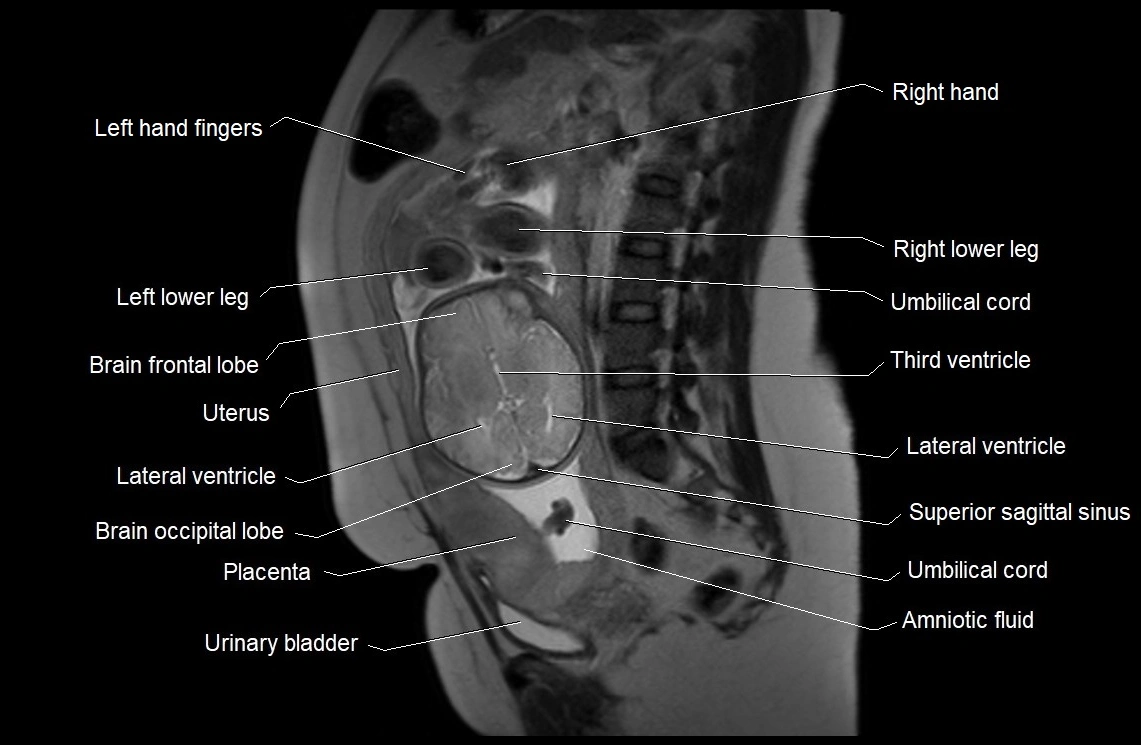

MRI Appearance

T2 HASTE (T2 GRE):

• Amniotic fluid shows very bright hyperintense signal

• Provides natural contrast against fetus and placenta

• Small particles (vernix) may appear as scattered hypointense foci within bright fluid

MRI image

image